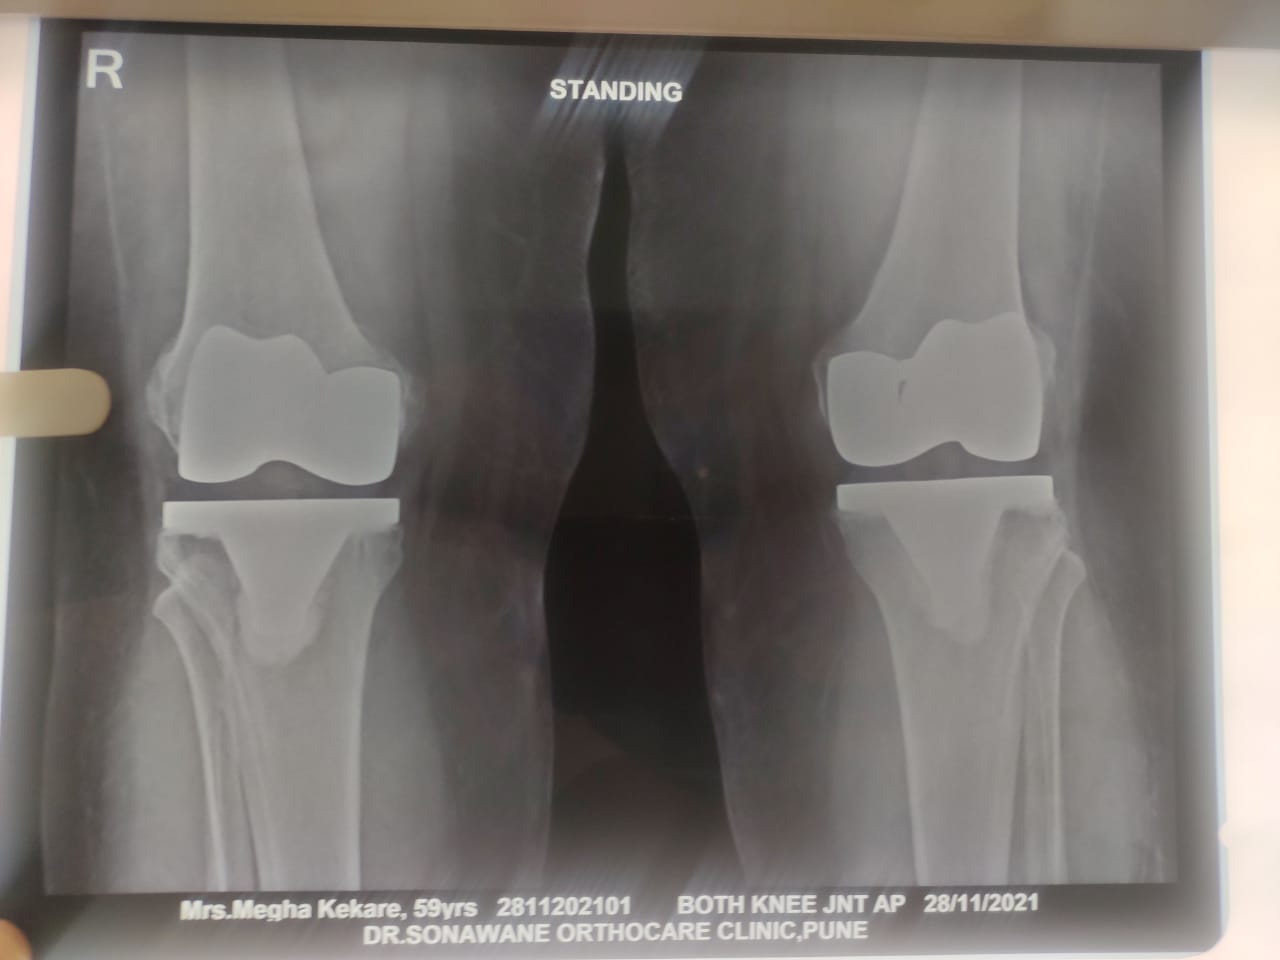

Dr. Sonawane Orthocare clinic is a centrally located Orthopedic Clinic In Pune city near Swargate at Hirabaug Business Centre, Hirabaug chowk, Tilak Road, Shukrawar peth and has easy accessibility from all parts of the city with multiple modes of travelling and enough parking spaces for patients’ own vehicles. Clinic is very modern and stylish and has air conditioned waiting area with comfortable sitting arrangement along with other amenities like TV, Wi-Fi, newspapers. There is hassle-free appointment and consultation system which is totally computerized. Patients get system generated appointment messages, reminders for follow-up dates and prescriptions through messages and emails. So its easy to keep track, keep and carry records and access it anywhere in the world. Clinic offers in-house digital X-ray, pathology tests and physiotherapy facilities at very reasonable rates. This makes the clinic a one stop destination for the patients they don’t need to go anywhere else for these facilities, saving lots of time and effort to get the treatment. We at Dr. Sonawane Orthocare clinic are committed for the best orthopedics care and proud to be one of the best orthopedics clinics in Pune.